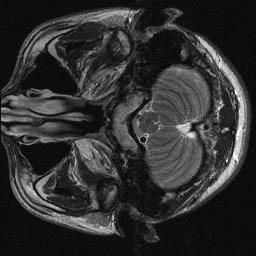

Magnetic resonance imaging serves as an essential tool for clinical diagnosis. However, it suffers from a long acquisition time. The utilization of deep learning, especially the deep generative models, offers aggressive acceleration and better reconstruction in magnetic resonance imaging. Nevertheless, learning the data distribution as prior knowledge and reconstructing the image from limited data remains challenging. In this work, we propose a novel Hankel-k-space generative model (HKGM), which can generate samples from a training set of as little as one k-space data. At the prior learning stage, we first construct a large Hankel matrix from k-space data, then extract multiple structured k-space patches from the large Hankel matrix to capture the internal distribution among different patches. Extracting patches from a Hankel matrix enables the generative model to be learned from redundant and low-rank data space. At the iterative reconstruction stage, it is observed that the desired solution obeys the learned prior knowledge. The intermediate reconstruction solution is updated by taking it as the input of the generative model. The updated result is then alternatively operated by imposing low-rank penalty on its Hankel matrix and data consistency con-strain on the measurement data. Experimental results confirmed that the internal statistics of patches within a single k-space data carry enough information for learning a powerful generative model and provide state-of-the-art reconstruction.